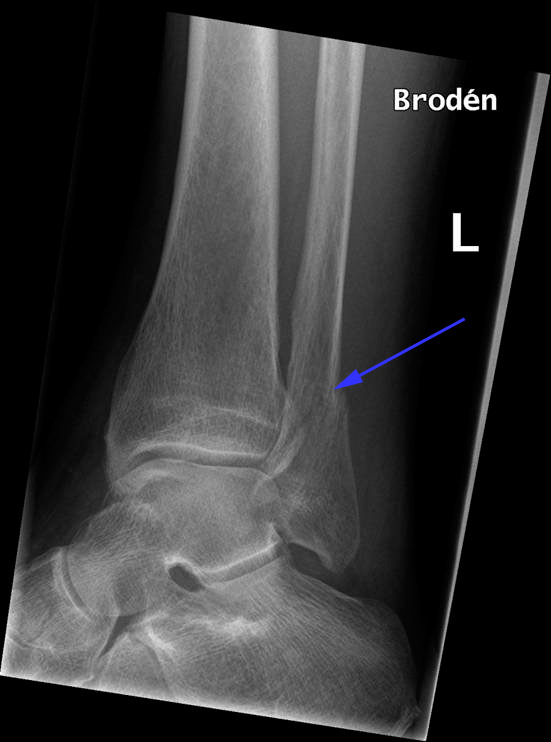

Klassisk fraktur (blå pil) af lægbenet (fibula) tæt på fodleddet – såkaldt  lateral malleolfraktur.